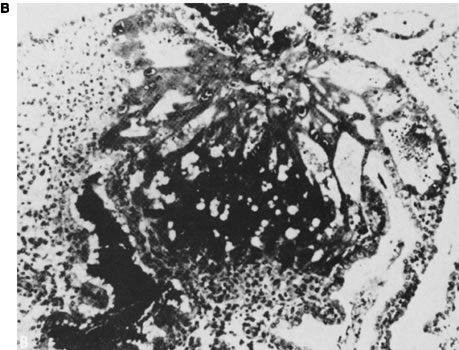

BeSt programmi toetusel valminud õpiobjekt "Korduv raseduse katkemine" on koostatud eesmärgiga anda sünnitusabi ja günekoloogia eriala spetsialistele, doktorantidele ja residentidele kaasajastatud ülevaade igapäevases kliinilises töös suhteliselt sageli esinevast probleemist. Õppematerjal koosneb nelja haigusjuhu analüüsist ja teoreetilisest osast, kus käsitletakse korduva raseduse riskitegureid, põhjusi ja ravi võimalusi. Õppematerjal sisaldab mitmeid testivormis küsimusi, mille abil saab hinnata oma teadmisi õppeprotsessi vältel. Kasutatud materjalid ja täiendavad infoallikad on toodud materjali lõpus teemade kaupa. Õppematerjali läbitöötamiseks kulub orienteeruvalt 10-12 tundi.